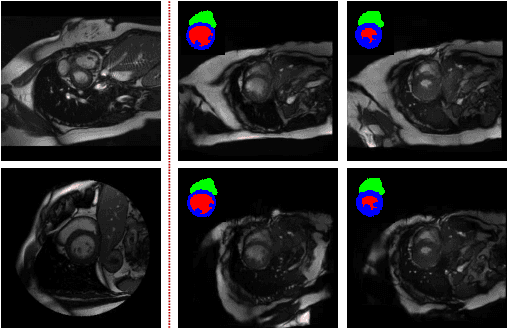

Abstract:Generative adversarial networks (GANs) have provided promising data enrichment solutions by synthesizing high-fidelity images. However, generating large sets of labeled images with new anatomical variations remains unexplored. We propose a novel method for synthesizing cardiac magnetic resonance (CMR) images on a population of virtual subjects with a large anatomical variation, introduced using the 4D eXtended Cardiac and Torso (XCAT) computerized human phantom. We investigate two conditional image synthesis approaches grounded on a semantically-consistent mask-guided image generation technique: 4-class and 8-class XCAT-GANs. The 4-class technique relies on only the annotations of the heart; while the 8-class technique employs a predicted multi-tissue label map of the heart-surrounding organs and provides better guidance for our conditional image synthesis. For both techniques, we train our conditional XCAT-GAN with real images paired with corresponding labels and subsequently at the inference time, we substitute the labels with the XCAT derived ones. Therefore, the trained network accurately transfers the tissue-specific textures to the new label maps. By creating 33 virtual subjects of synthetic CMR images at the end-diastolic and end-systolic phases, we evaluate the usefulness of such data in the downstream cardiac cavity segmentation task under different augmentation strategies. Results demonstrate that even with only 20% of real images (40 volumes) seen during training, segmentation performance is retained with the addition of synthetic CMR images. Moreover, the improvement in utilizing synthetic images for augmenting the real data is evident through the reduction of Hausdorff distance up to 28% and an increase in the Dice score up to 5%, indicating a higher similarity to the ground truth in all dimensions.

Abstract:We propose a hybrid controllable image generation method to synthesize anatomically meaningful 3D+t labeled Cardiac Magnetic Resonance (CMR) images. Our hybrid method takes the mechanistic 4D eXtended CArdiac Torso (XCAT) heart model as the anatomical ground truth and synthesizes CMR images via a data-driven Generative Adversarial Network (GAN). We employ the state-of-the-art SPatially Adaptive De-normalization (SPADE) technique for conditional image synthesis to preserve the semantic spatial information of ground truth anatomy. Using the parameterized motion model of the XCAT heart, we generate labels for 25 time frames of the heart for one cardiac cycle at 18 locations for the short axis view. Subsequently, realistic images are generated from these labels, with modality-specific features that are learned from real CMR image data. We demonstrate that style transfer from another cardiac image can be accomplished by using a style encoder network. Due to the flexibility of XCAT in creating new heart models, this approach can result in a realistic virtual population to address different challenges the medical image analysis research community is facing such as expensive data collection. Our proposed method has a great potential to synthesize 4D controllable CMR images with annotations and adaptable styles to be used in various supervised multi-site, multi-vendor applications in medical image analysis.